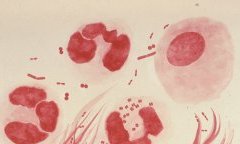

Woleu-Ntem : Le taux de prévalence au VIH/Sida déjà parmi les plus élevés du Gabon

La province du Woleu-Ntem a célébré, le 1ᵉʳ décembre 2025, la 37ᵉ Journée mondiale de lutte contre le Sida dans un contexte...